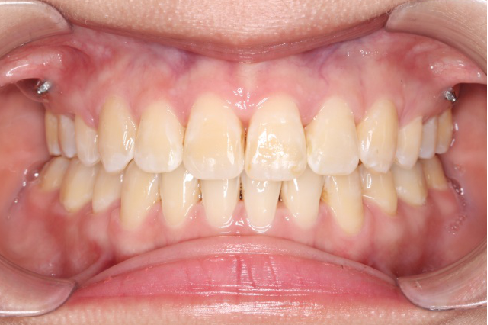

2018.11.14  术后磨牙尖牙I类关系,中线齐,覆合,覆盖正常

迷你观评价:上下牙齿中线与面中线对齐,笑弧协调,微笑时牙龈暴露量正常,微笑时横向正常,左右唇基本对称。

微观评价:牙齿整齐,咬合关系良好,上下前牙转矩及突度控制良好,磨牙关系I类,尖窝咬合关系良好,OB,OJ正常。